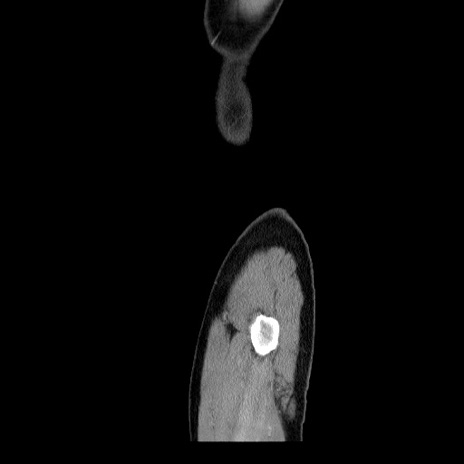

横断像